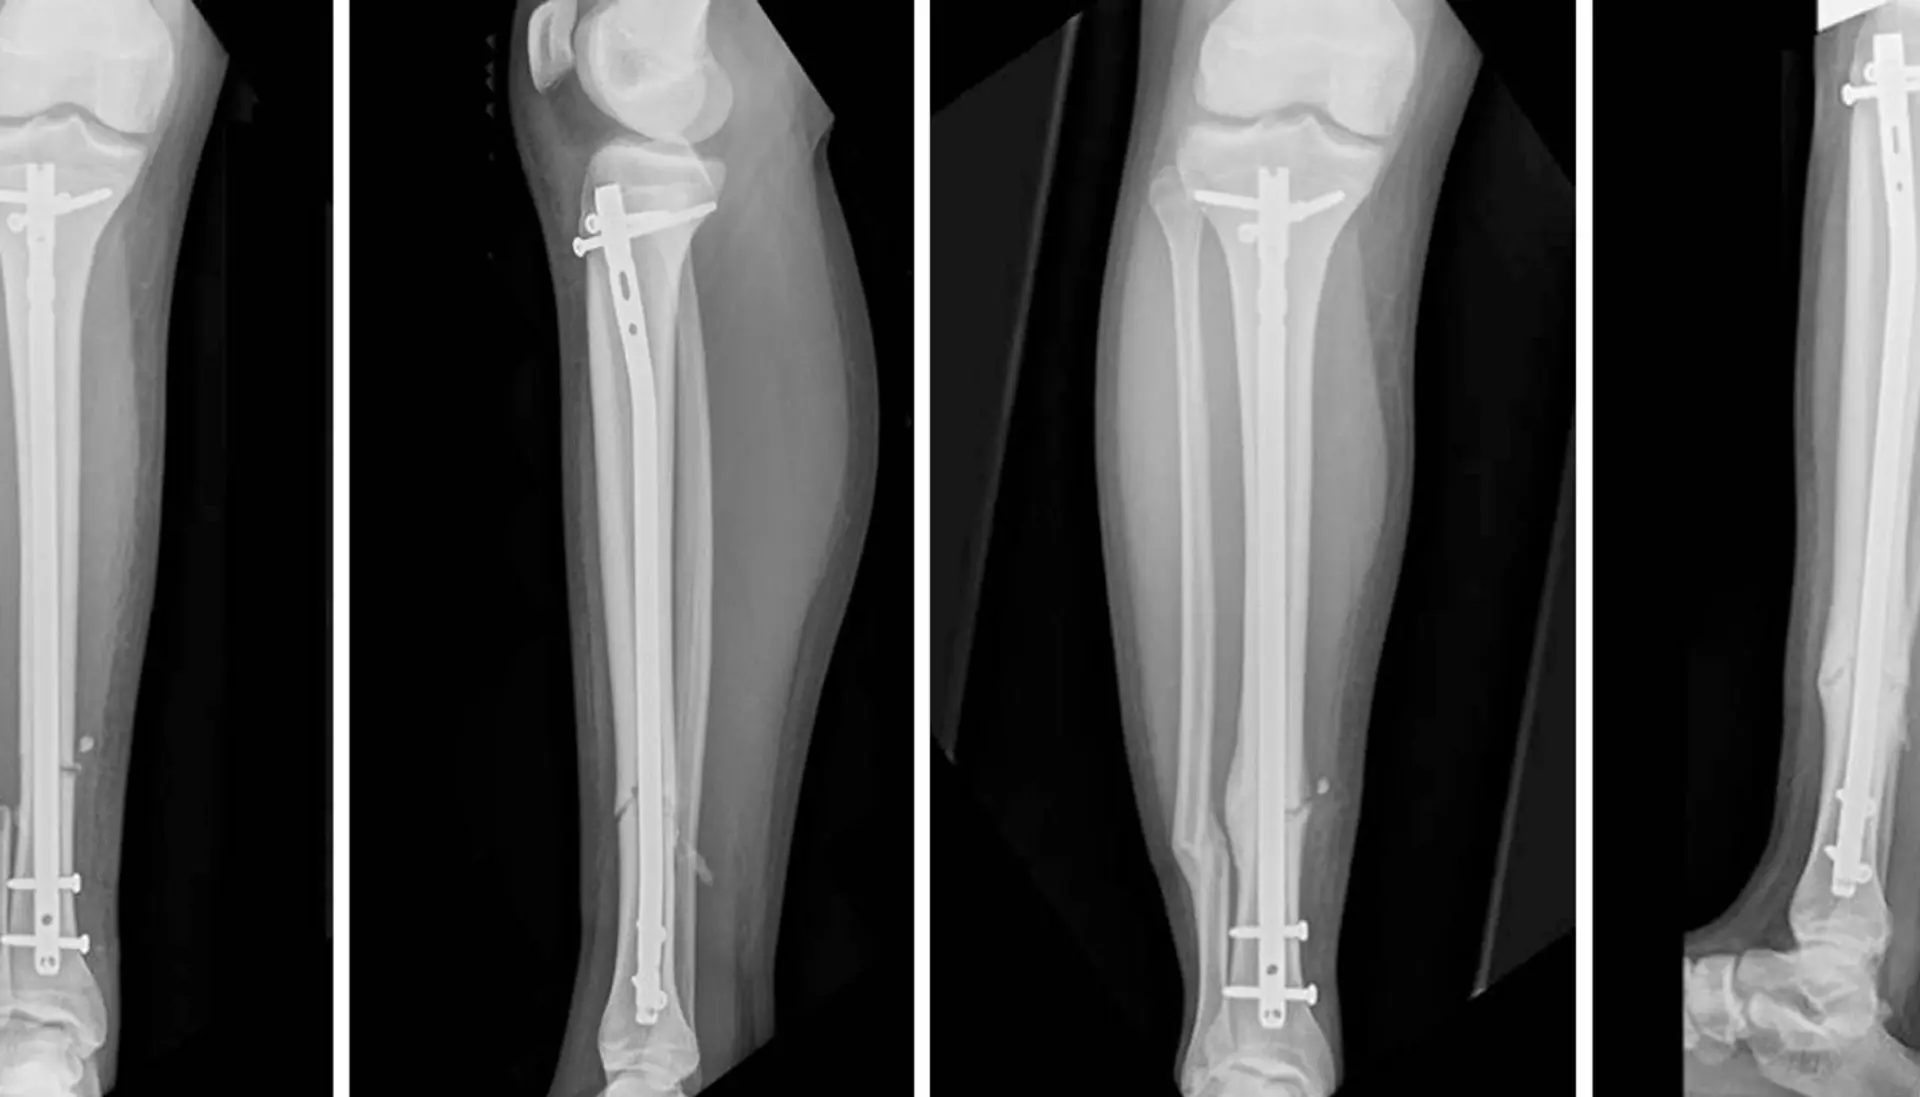

Standard intramedullary nails are cylindrical rods placed inside the medullary cavity of long bones.

It is a surgical procedure by which a IM nail introduce into medulla of the bone to fix the bone correct place.

Interlocking nails:

Inter-locking nail is a metal rod forced into the medullary cavity of a bone. IM nails have long been used to treat fractures of long bones of the body.

1) Fracture of tibia at different s level.

2) Comminuted fractures.

3) Segmental fractures.

4) Proximal and distal third fractures.